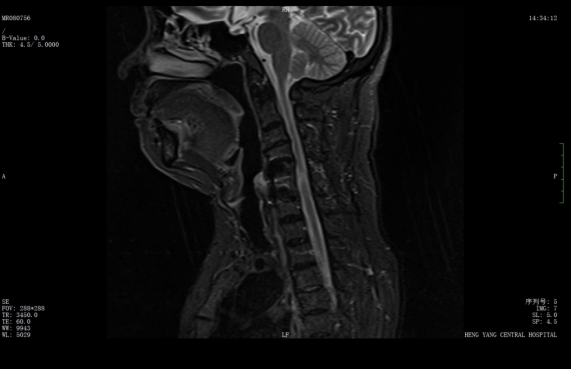

該患者此前因膽囊結(jié)石祁東縣人民醫(yī)院治療,來(lái)自衡陽(yáng)市中心醫(yī)院駐該院副院長(zhǎng)李攀峰為其主刀進(jìn)行手術(shù),術(shù)后患者恢復(fù)良好。后因突發(fā)四肢癱瘓、生活無(wú)法自理,為尋求進(jìn)一步治療,經(jīng)醫(yī)聯(lián)體通道轉(zhuǎn)入衡陽(yáng)市中心醫(yī)院。脊柱外科錢軍博士團(tuán)隊(duì)接診后,迅速組織詳細(xì)問診、體格檢查及系統(tǒng)術(shù)前評(píng)估。查體顯示患者四肢關(guān)鍵肌肌力僅I級(jí),感覺功能明顯減退,結(jié)合影像學(xué)結(jié)果,診斷為頸脊髓損傷伴不全癱,有明確手術(shù)指征。

術(shù)前核磁共振提示:頸椎椎管狹窄、頸脊髓信號(hào)改變